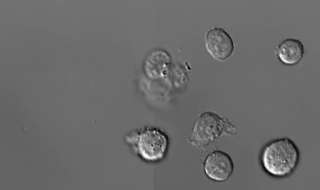

Заснеха видео на смъртта на левкоцититеАвстралийски учени са заснели за първи път в историята видео на смъртта на левкоцитите (белите кръвни клетки) в човешкия организъм, съо ...18.06.20152 0780 -